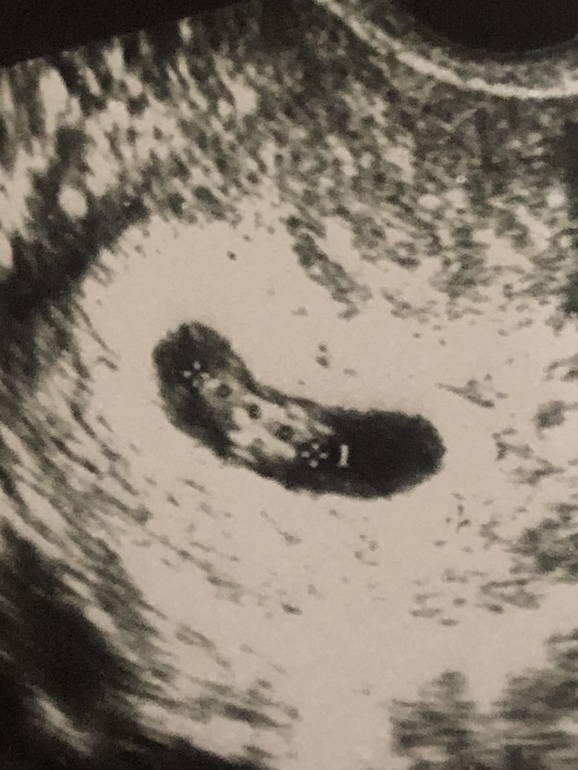

И второй вопросик, кто понимает узи, что за три кругляшка у эмбриончика?